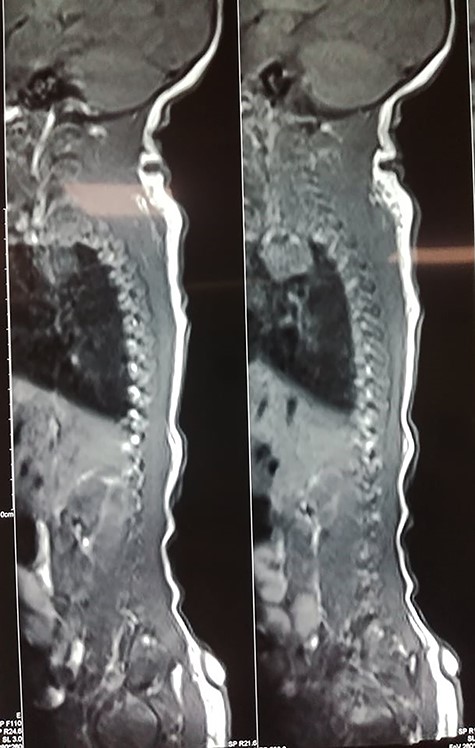

Magnetic resonance imaging (MRI) of the spine showed no evidence of spinal dysraphism, suspecting the diagnosis of a true human tail (Fig. 2).

Surgical management was performed: a midline lozenge incision was done encircling the base of appendage. The subcutaneous lipoma was excised and there were no connection with soft tissue or sacroma as shown in the MRI (Fig. 2).

Human tails may be associated with other congenital anomalies in 29% of cases and review of the literature showed spina bifida to be the most frequent coexisting anomaly with both true tail and pseudotail [8]. In our case, the MRI invalidated any associated spine anomaly.